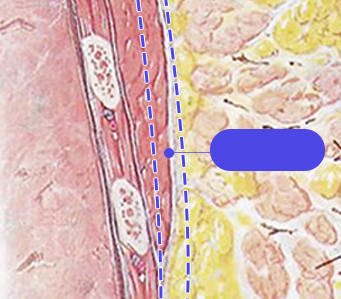

筋膜

利用内视镜剥离胸部肌肉时,零损伤保存筋膜的同时不会导致皮肤变薄,更能保证术后胸部触感自然真实.

因内视镜剥离技术欠缺造成筋膜损伤的情况,损伤的筋膜后面存有的脂肪流出来使皮肤变薄,导致容易触摸到假体且触感不自然.

颜美HD内视镜胸部整形通过熟练的专业技术保存筋膜的同时,保证术后触感自然真实.

零损伤筋膜保存术

胸部触感更加自然真实